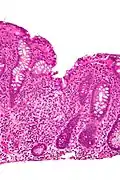

Cryptitis. H&E stain.

In histology, cryptitis refers to inflammation of an intestinal crypt.

Cryptitis is a non-specific histopathologic finding that is seen in several conditions, e.g. inflammatory bowel disease,[1] diverticular disease,[2] radiation colitis,[3] infectious colitis.